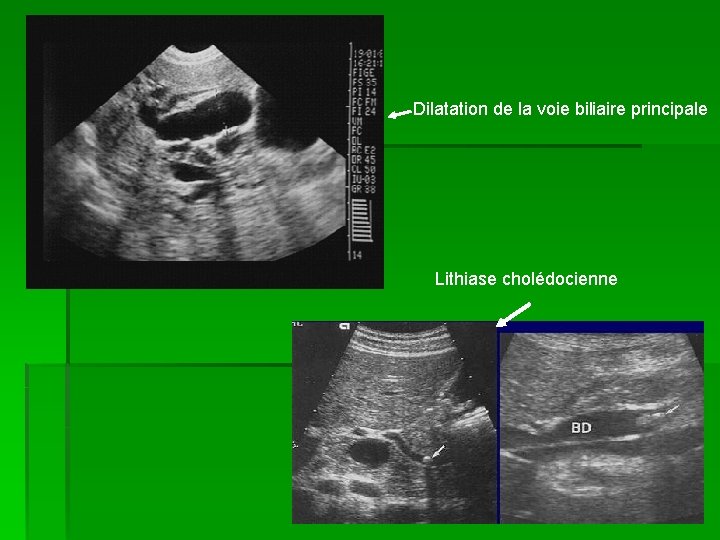

Lithiase Biliaire – Echo-Urgences

Lithiase biliaire – Echo-Urgences echo-urgences.com

La Lithiase De La Voie Biliaire Principale (LVBP) Et Complications

La lithiase de la voie biliaire principale (LVBP) et complications slideplayer.fr